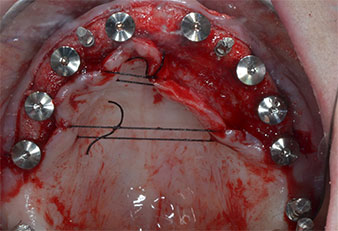

Три години по-късно е дошло времето за максиларна протеза от същия тип. Въз основа на планирането със CBCT, аугментацията на синусите е избегната с помощта на къси импланти и използването на хирургичен шаблон, за да се прехвърлят планираните позиции в алвеоларния гребен. (Фиг. 1 и 2).

Пиезоелектрически инструмент с диамантено покритие с форма на пламък (Piezomed I1) e използван за маркиране на позициите на имплантите и за пилотна подготовка (Фиг. 3). Препарацията беше извършена с внимателни вертикални движения, с намалена мощност, пълна иригация и лек натиск (под 300 g) След това се приложи пилотен инструмент (Piezomed I2A/ I2P) за първоначално увеличение на диаметъра на имплантното ложе с 2 mm (Фиг. 4), последвано от 3 mm разширение (Фиг. 5)